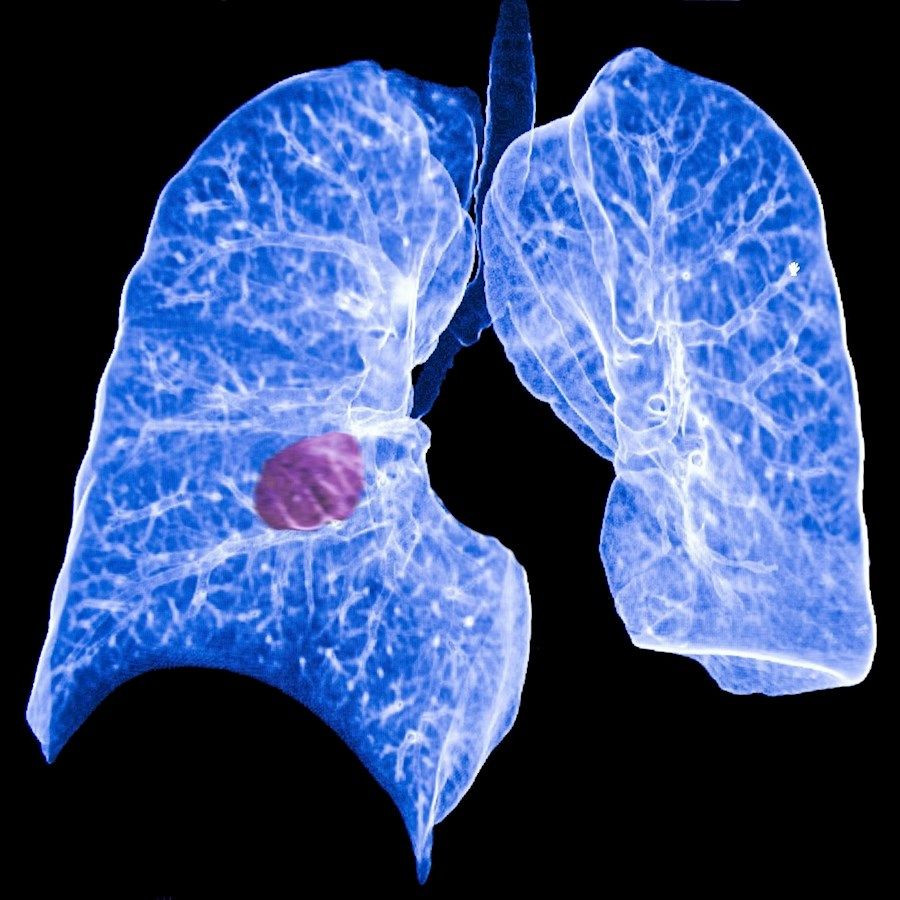

Investigadores de la Universidad de Tulane han identificado marcadores que pueden predecir si es probable que el cáncer de pulmón se propague, lo que supone un importante avance ya que actualmente no hay pruebas que permitan a los médicos identificar pacientes donde una terapia más agresiva podría reducir la mortalidad.

Se trata de una proteína en vesículas extracelulares derivadas de tumores que indica si es probable que un cáncer de pulmón de células no pequeñas (CPCNP) metastatice, según un nuevo estudio publivado en la revista `Science Advances`.

Es el cáncer diagnosticado con mayor frecuencia y la principal causa de muerte por cáncer en todo el mundo, y más de la mitad de los pacientes mueren después de desarrollar metástasis.

La mayoría de los pacientes con CPCNP no son diagnosticados hasta que su tumor primario ha hecho metástasis a otras partes del cuerpo. Sin embargo, incluso los pacientes diagnosticados con tumores no metastásicos de la misma etapa a menudo pueden tener resultados de tratamiento muy diferentes.